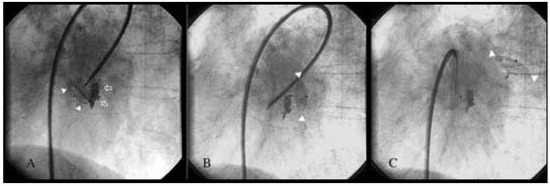

An 80-year-old woman with symptomatic rheumatic mitral valve disease and chronic atrial fibrillation was admitted for mitral valvuloplasty and interventional occlusion of the left atrial appendage. Mitral commissurotomy had been performed 30 years earlier. Because of unstable INR with warfarin therapy, she was at increased risk for bleeding and thromboembolism. The left atrium was grotesquely dilated (10.3 × 4.6 cm) and showed spontaneous echo contrast. Severe calcification of the mitral valve and mitral annulus resulted in significant stenosis (mitral valve area 1.0 cm2, mean pressure gradient 11 mm Hg) and mild mitral regurgitation. The coronary arteries were normal and mitral valvuloplasty was performed resulting in only moderate improvement with a valve area of 1.3 cm2. After fluoroscopic identification of the atypically located left atrial appendage by contrast medium injection, a 10 mm Amplatzer septal occluder was inserted (fig. 1A). However, after its detachment from the catheter, the device dislodged from the left atrial appendage and was found floating in the left atrium (fig. 1B, C). In light of the residual mitral stenosis with moderate regurgitation, no attempt was made to retrieve the dislodged device percutaneously. The patient was left with bed rest and heparin. The next day the device was still in the left atrium (fig. 2) and mitral valve replacement was performed. The occluder was removed from the left atrium and found clean from thrombosis (fig. 3). An atrial septal tear resulting from the transseptal puncture was repaired, and the left atrial appendage was obliterated. Postoperative recovery was uneventful.

Figure 1. A. Atypically located left atrial appendage outlined with contrast medium (arrows) with the 10 mm Amplatzer septal occluder inserted (arrowheads). B, C. Occluder (arrowheads) dislodges into left atrium after detachment from the catheter.